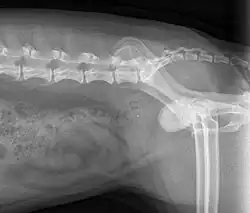

When symptoms indicate bladder stones, the first step is usually to take an x-ray. Most types of stones will appear readily in an x-ray, urate and occasionally cystine stones being the most common exceptions. Stones smaller than three millimeters may not be visible.[4] Ultrasonography is also useful for identifying bladder stones. Crystals identified in a urinalysis may help identify the stones, but analysis of the stones is necessary for identification of the complete chemical composition.